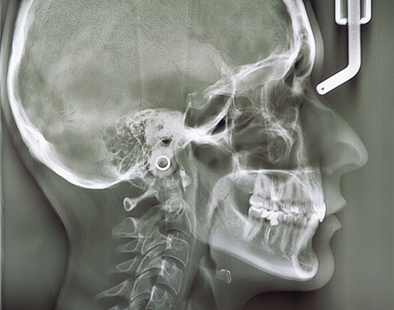

質の高い治療を患者様へお届けするためには、各設備を充実させる必要があります。当院では歯科用CT、セファロ、口腔内スキャナー、CAD/CAMシステム、CO2レーザー、エアフローなど各種専門の先端設備を導入しております。また、手術時には無影灯付きの専用オペ室にて、精度高く治療いたします。

セファロ